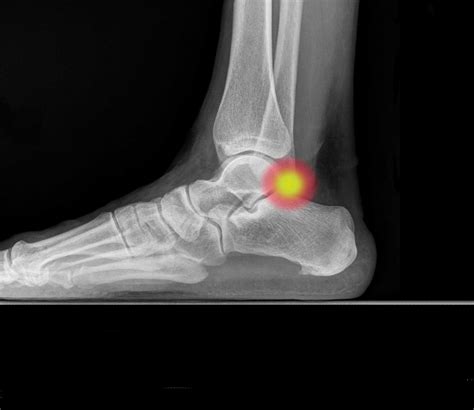

OS TRIGONUM SYNDROME